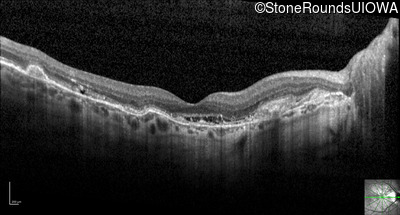

Optical Coherence Tomography - Right - 20/25 +1

Exemplar / OCT Stack

OCT Stack